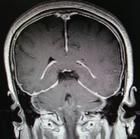

3. 頭顱MRI 增強:顯示廣泛性瀰漫性腦膜增厚。